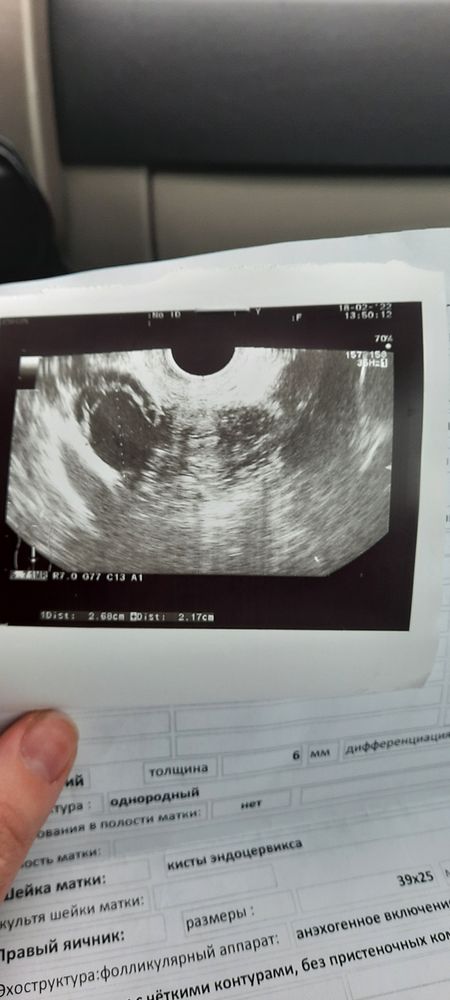

Подскажите пожалуйста это нормально, это могут забеременеть?

Есть ДФ 26 мм, уже перерос тает в кисту, но легко может совулировать сегодня-завтра, Б не исключена. Эндометрия хватает для Б.

Похоже на фолликулярную кисту. Должно быть узи ещё в динамике через цикл, если киста на месте, то лечение на 1-3 месяца, а потом опять узи.

Недостаточность желтого тела Первое узи